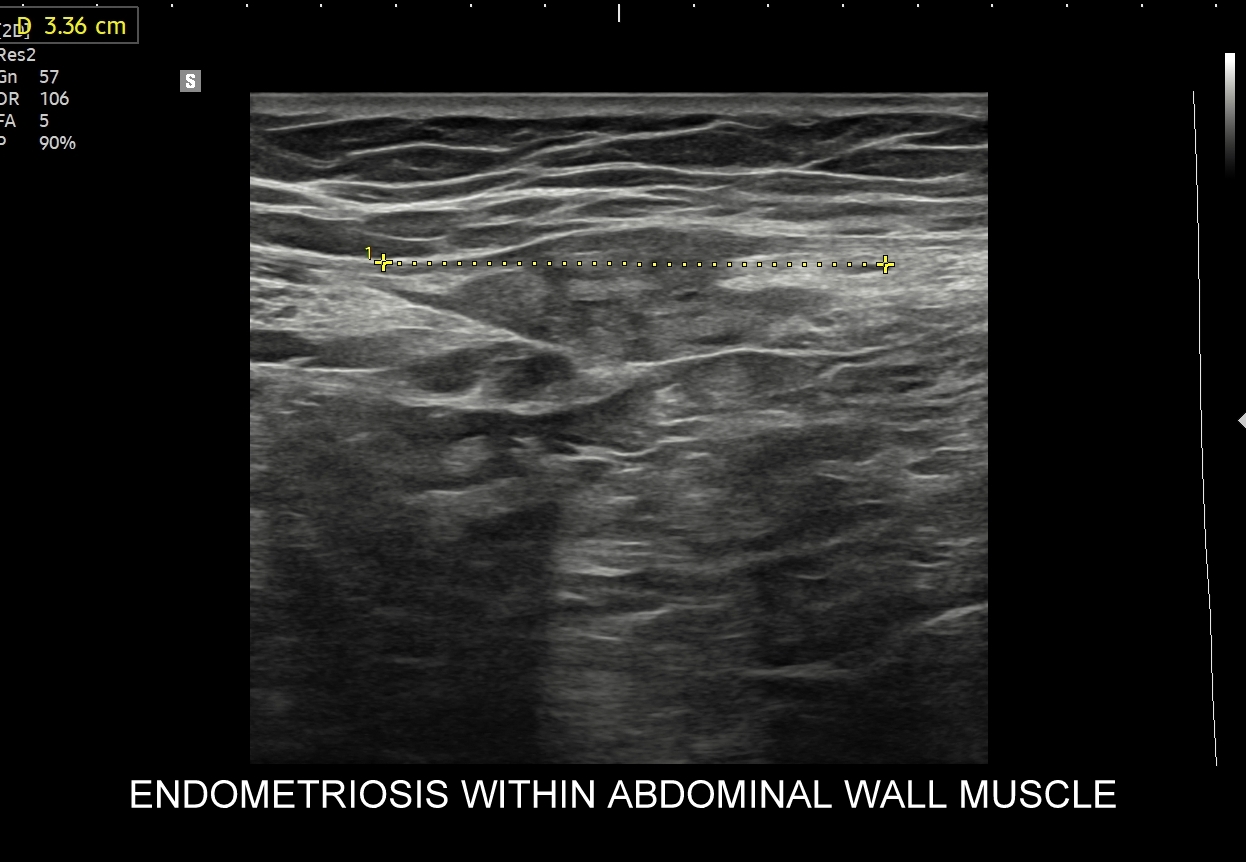

Makroskopowo endometrioza przyjmować może różnorodne formy morfologiczne. Endometrioza powierzchowna cechuje się powstawaniem guzków lub płaskich nacieków na powierzchni narządów miednicy i jamy otrzewnowej. Endometrioza głęboka charakteryzuje się głębokim naciekaniem do struktur przestrzeni pozaotrzewnowej, powłok brzucha oraz narządów miednicy; a przyjmuje m. in. takie formy jak guzki, torbiele, deformacje i skaryfikacje. W jamie otrzewnowej może przybierać również postać zwłóknień i zrostów. Z kolei w układzie rozrodczym w jajnikach przyjmuje formę tzw. torbieli czekoladowej, a w ścianie macicy adenomyozy. Najczęstsze lokalizacje endometriozy obejmują jajniki, otrzewną miednicy mniejszej, zatokę Duglasa, więzadło maciczno-krzyżowe, blizny po cięciu cesarskim.

W badaniu USG ogniska endometriozy zwykle przyjmują formę hypoechogennych guzków i nieregularnych mas; mogą być niejednorodne echogenicznie i zawierać drobne obszary torbielowate; w trybie color-Doppler i MVI wykazują skąpe unaczynienie.

Na skanach w niniejszym artykule zaprezentowany jest przypadek endometriozy głębokiej w miednicy mniejszej z intraluminalnym nacieczeniem dystalnego odcinka moczowodu, jego całkowitą niedrożnością i wtórnym wodonerczem. Choroba w tak zaawansowanym stadium wykryta została przypadkowo w rutynowym przezbrzusznym badaniu USG jamy brzusznej. W ramach diagnostyki różnicowej przeprowadzone zostały badanie CT, MRI oraz ureterocystoskopia z pobraniem materiału do badania histopatologicznego, na podstawie którego postawiono rozpoznanie endometriozy.